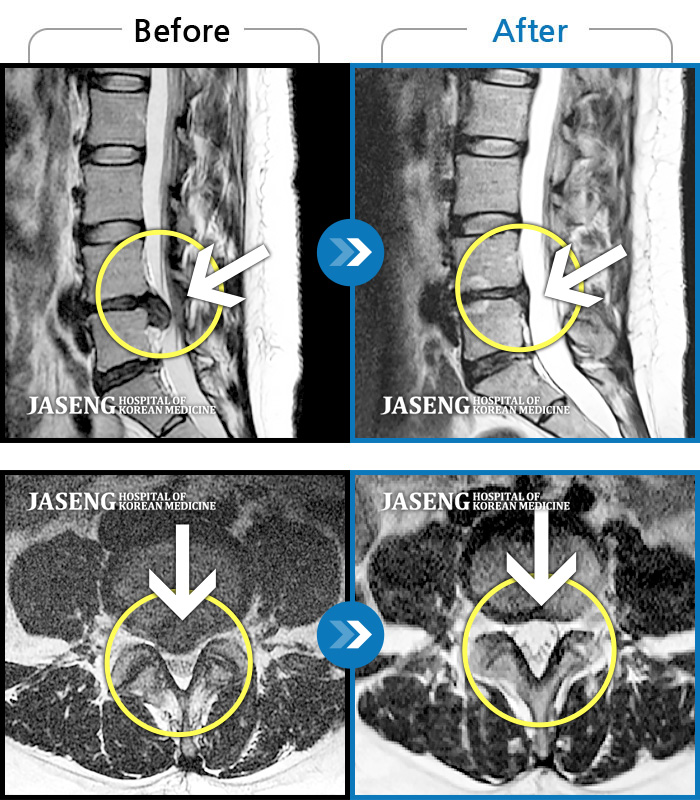

Before

After

환자에게 사전 동의를 받아 동일 조건에서 촬영되었습니다.

개인에 따라 치료 후 부작용이 발생할 수 있으니 의료진과 상담 후 치료를 진행하시기 바랍니다.

허리와 다리에 찌르는 듯한 통증

허리 통증 및 좌측 다리 마비 증상